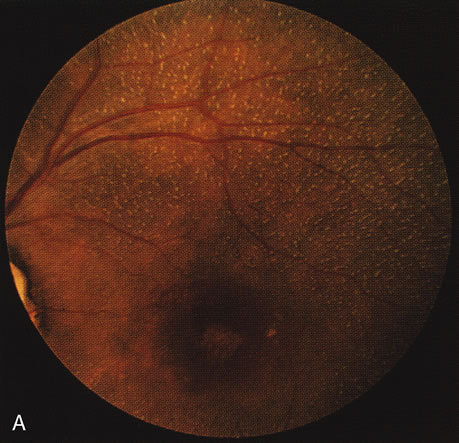

When the macula has typical superficial linear plications radiating from the fovea seen with schisis (e.g., juvenile retinoschisis, Goldmann-Favre disease), FA is normal (Fig. 8A and B). This indicates that the pathology is in the inner retina (probably Henle's fiber layer, considering the spokewheel pattern). However, when the schisis flattens, it is not uncommon to see a transmitted hyperfluorescence suggesting a secondary atrophy to the RPE (Fig. 8C and D).

Fig. 8. Juvenile XLR retinoschisis. The superficial macula schisis (A) does not affect the angiogram (B) except in a few areas where it has flattened and resulted in some pigment dispersion. When the macular schisis has entirely flattened (C) there is a mild transmission hyperfluorescence (D). At this stage the diagnosis can be suspected by the presence of an inferior retinoschisis (present in half) and confirmed by the typical electroretinographic finding of a scotopic electronegative response (present in all affected males).

The periphery may show schisis or vascular sheathing. Histopathology of the peripheral schisis in juvenile retinoschisis documents a splitting of the nerve fiber layer.13 FA shows retinal vascular abnormalities, including capillary nonperfusion, focal and diffuse vascular leakage, and intraretinal neovascularization, in many of these disorders.14 These may or may not be associated with schisis.